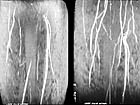

leg

arteries, before and after gene therapy, courtesy Jeffrey Isner, MD

Another method

of promoting angiogenesis is through gene therapy, one of the

newest and most promising

areas of research in the field of heart disease. Ultimately,

this will be a catheter-based technology, delivering genetic

material directly to the arterial wall, so that, in the words

of the popular media, you can "grow

your own bypass". There are clinical trials currently under way and the results

have been very encouraging. See a (video

interview with Dr. Jeffrey Isner of St. Elizabeth's Hospital in Boston about

the results of his study.) |